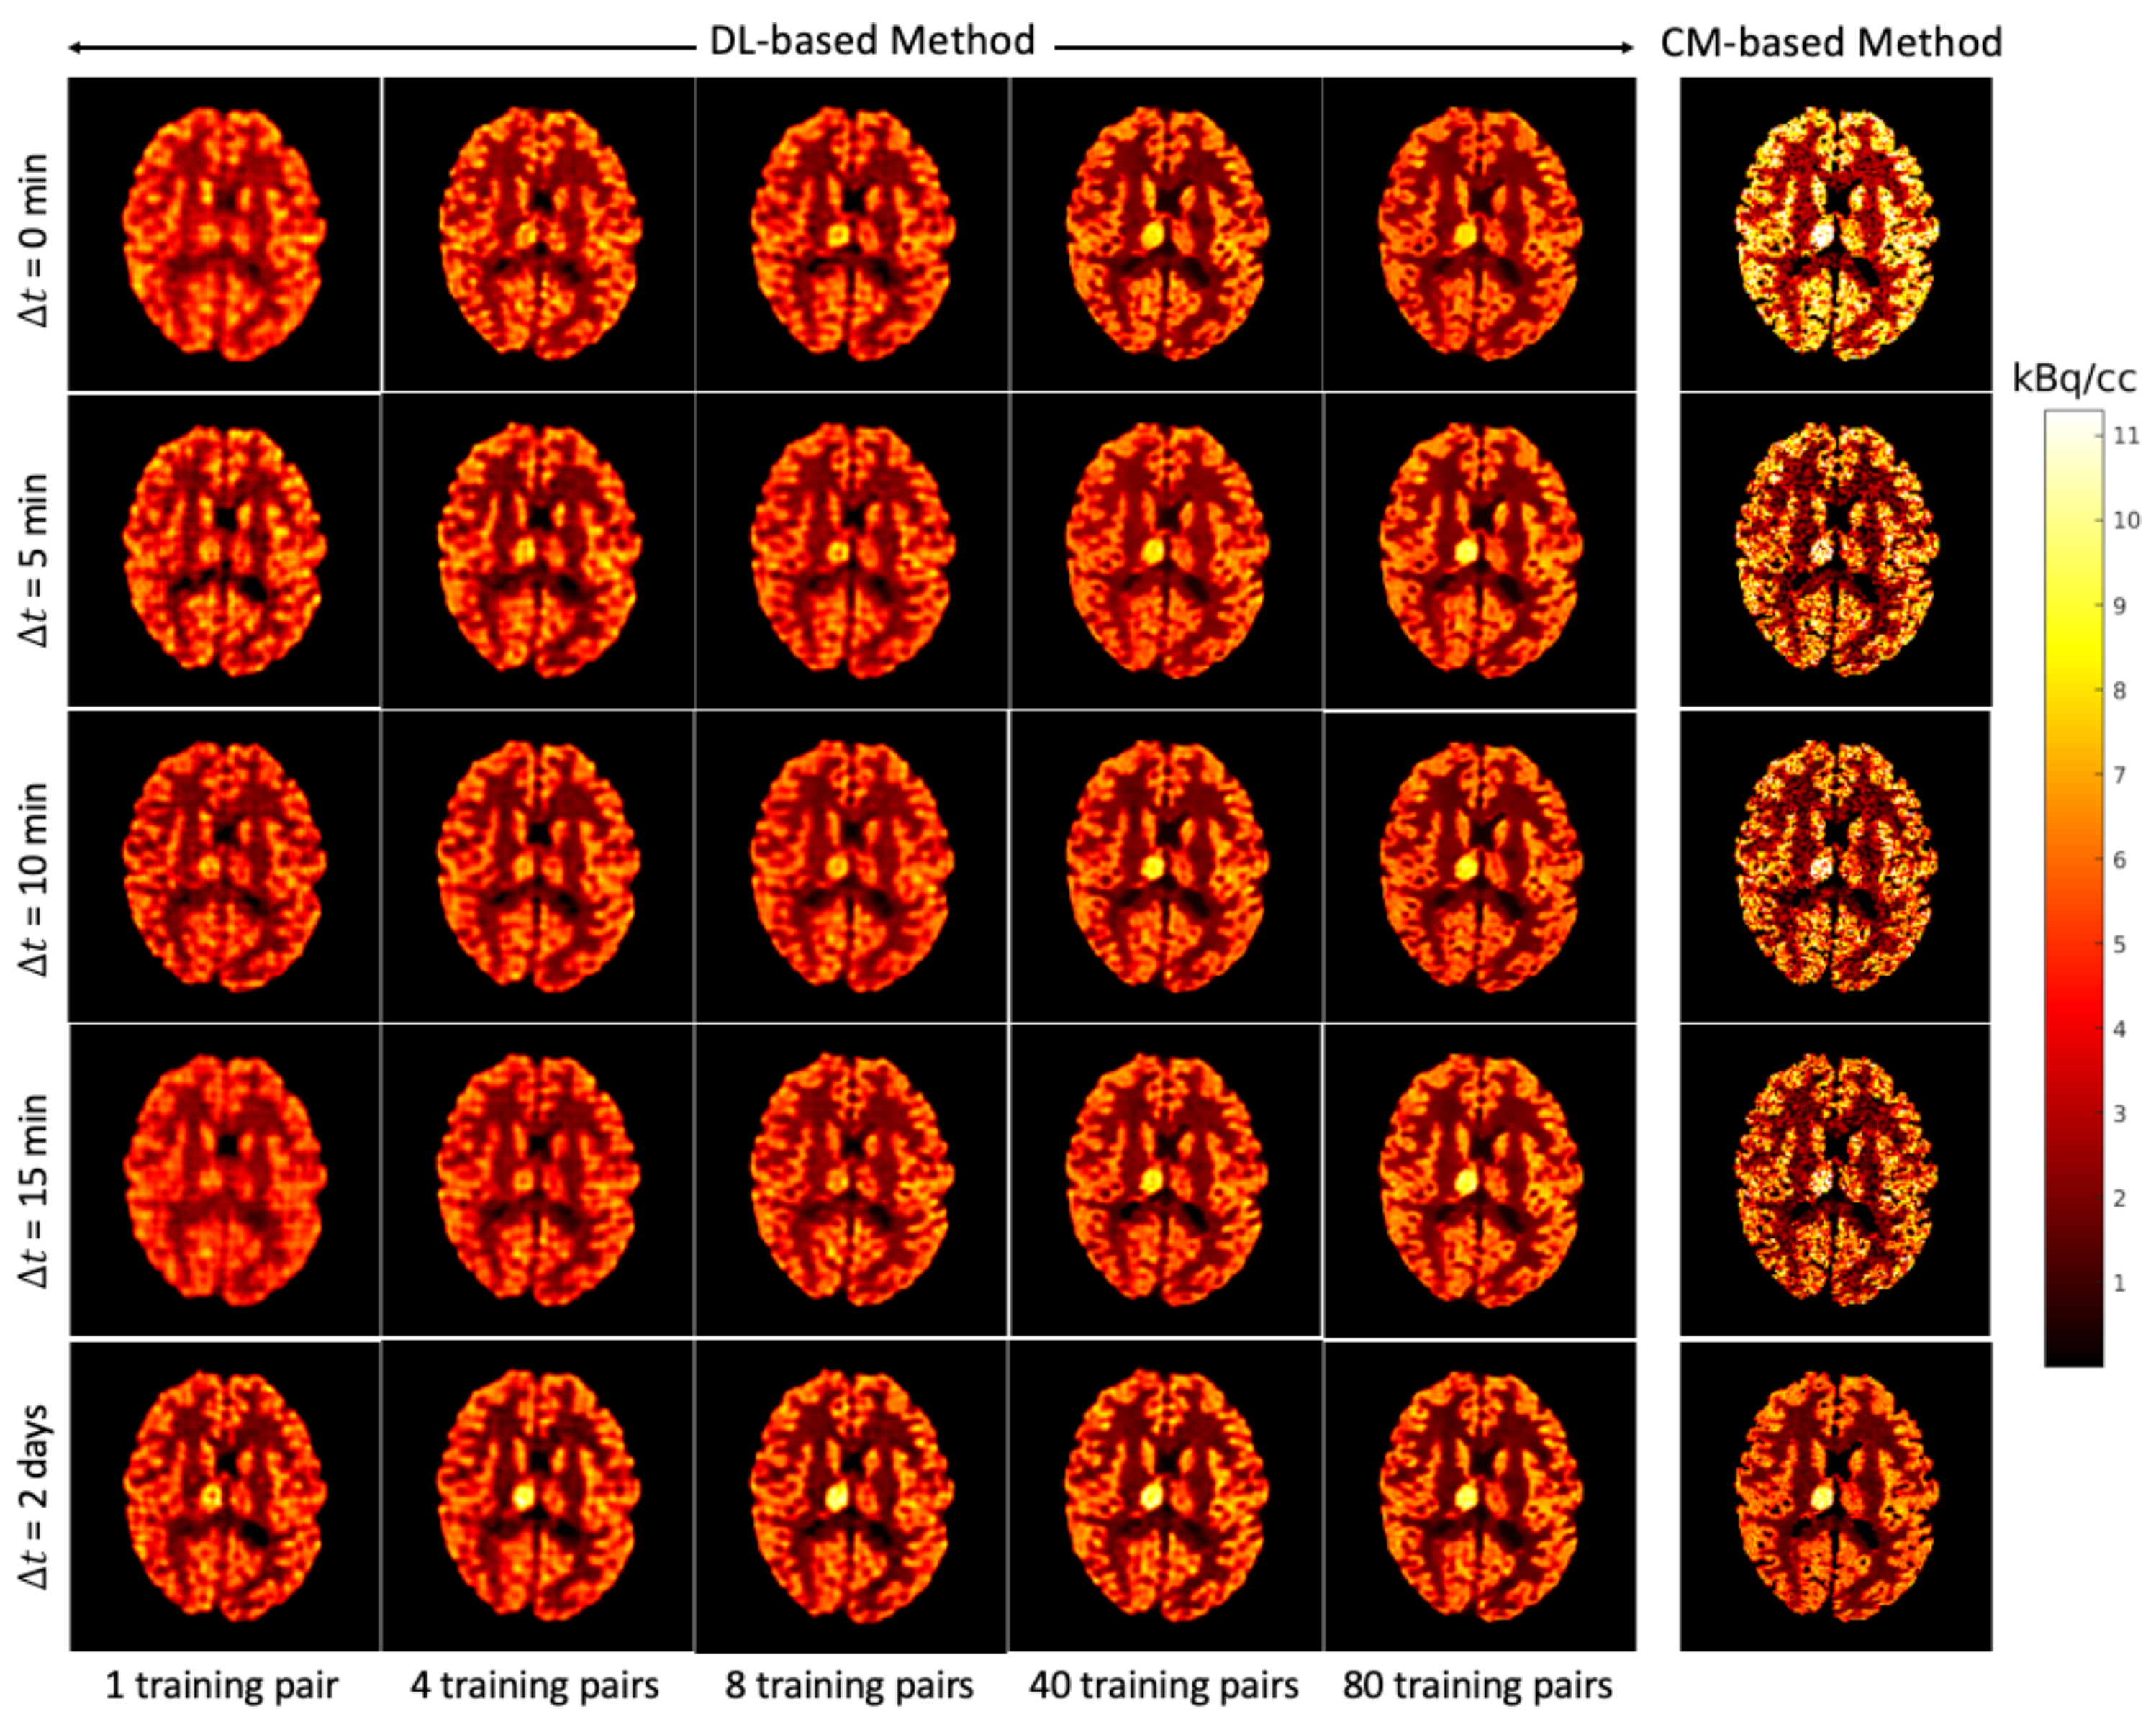

Figure 7 shows for each that the average NRMSE decreases and that a smaller SD is obtained in the test set as the number of training pairs increases from 1 to 80. This is consistent with the visual impression of the separations obtained by the DL-based method, as shown in Figure 8 and Figure 9. The first to fifth columns display the separated static single-tracer images (activity distributions) based on different numbers of training pairs (for plotting only, we limit the colour scale of the figures to fall within the same range as the reference images in Figure 6b for and Figure 6e for , respectively). Although all cases successfully recover the separated images, using more training pairs results in higher separation performance in terms of recovering the tumour regions, shapes and low contrast of the white and grey matter for . Figure 10a,c also suggest that the more training pairs used, the better the average NRMSE, which is in line with the results shown in Figure 7. With 80 training pairs, the DL-based method achieved average NRMSE values for FDG and MET of ∼15% and ∼12%, respectively, for the test set across all (see the magenta lines in Figure 10a,c).

Figure 8.

Brain phantom (whole brain region): the static images recovered using the DL-based method (Columns 1 to 5) and the CM-based method (Column 6).

A test example of the separated images using the CM-based method is shown in the last column of Figure 8 (FDG) and Figure 9 (MET) for different . Compared to the results obtained from the DL-based method, the separated images using the CM-based method are much noisier because the model fitting (4) may fall into local minima even when the noise level is low. Although several strategies, such as using differing initial values or an exhaustive search algorithm [22], have been suggested to reduce local minima, their use in clinical practice is challenging because of their high computational cost.

4.3. DL-Based Method and CM-Based Method Comparison

The separation results between the DL-based method and CM-based method applied to the reconstructed dynamic dual-tracer noisy MLEM images were compared. For = 0, 5, 10 and 15 min, Figure 8 and Figure 9 show that in terms of visual assessment the CM-based method produces much nosier separated images than the DL-based method. This observation is consistent with better average NRMSE values of the DL-based separation results as illustrated in Figure 10. When using only 1 training pair, the DL-based method achieved high average NRMSE values across all (∼25% for FDG and ∼22% for MET). However, it nevertheless produces better average NRMSE values for = 0, 5, 10 and 15 min when compared to the separation results using the CM-based method. In fact, there are TACs contained in 1 training pair, one for each voxel; hence, in this instance, the proposed network was trained using TACs. Note that the DL-based method utilises both spatial and temporal information of the TACs from all voxels, but the CM-based method was implemented voxel by voxel, meaning only temporal information of one TAC was considered at each time. Therefore, for = 0, 5, 10 and 15 min, the DL-based method with 1 training pair yields better separation performance. When = 2 days, the CM-based method, in contrast to the DL-based method with 80 training pairs, achieved lower average NRMSE values for both FDG and MET. We believe this is the result of not enough training data which includes the case of = 2 days.